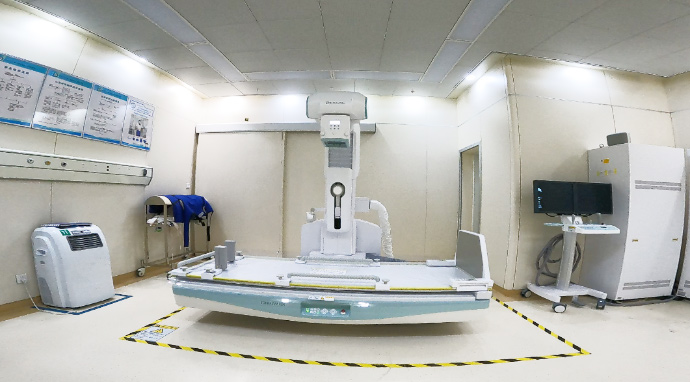

数字化多功能胃肠机(SONIALVISION SMIT)的Smart BMD(骨密度测量功能),通过对腰椎、髋关节部位进行DXA检查,可以很容易地检测出骨密度情况。患者在做骨密度测量的同时可以进行脆性骨折、压迫性骨折等X线检查。这样可以减少病人在不同检查室之间的移动,缩短检查时间,提高检查效率,降低了病人的负担。可在透视下进行操作,操作简单、定位准确、采集速度快。

图2 测量步骤